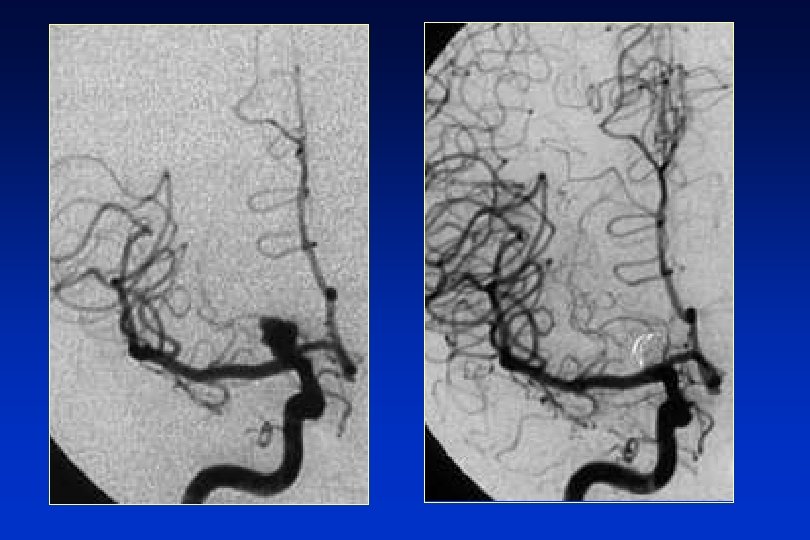

EXPLORACIONES COMPLEMENTARIAS l Tomografía computerizada: La sensibilidad de la TC > 90% primeras 24 horas. l Patrones aneurismáticos. l HSA perimesencefálica. l Sospecha y TC negativa: punción lumbar (PL) l Angiografía: FUNDAMENTAL q Lo más pronto posible. q Terapia endovascular.

Complicaciones HSA Resangrado (inmediato) l Cerrar el aneurisma l Vasoespasmo (segunda semana) -> isquemia secundaria l Nimodipino, Magnesio l Terapia triple H (hidratación, hipertensión, hemodilución) l Angioplastia l Hidrocefalia (primeros días) l Derivación externa o shunt ventrículo-peritoneal l

HSA TRATAMIENTO: medidas específicas l Prevención del resangrado: l Exclusión del aneurisma mediante cirugía l Exclusión del aneurisma por terapia endovascular l Fármacos antifibrinolíticos